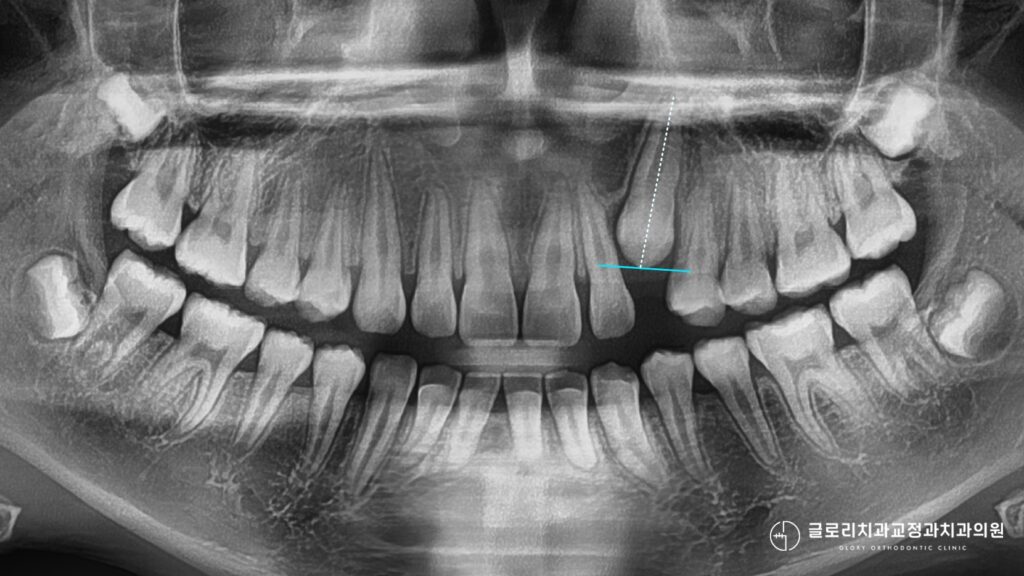

위 사진에서 확인할 수 있듯이 파노라마 엑스레이를 통해 치아 전체의 맹출 상태를 파악할 수 있습니다.

그러나 매복된 송곳니의 정확한 위치와 주변 치아 뿌리와의 관계를 확인하려면 CT 촬영이 필수적으로 병행되어야 합니다.

3차원 영상 자료를 통해 매복치가 입천장 쪽에 위치하는지 아니면 입술 쪽에 매복되어 있는지를 명확하게 구분할 수 있습니다.

이 위치에 따라 치료 방향이 달라지기 때문에 초기 진단의 정확성이 중요합니다.